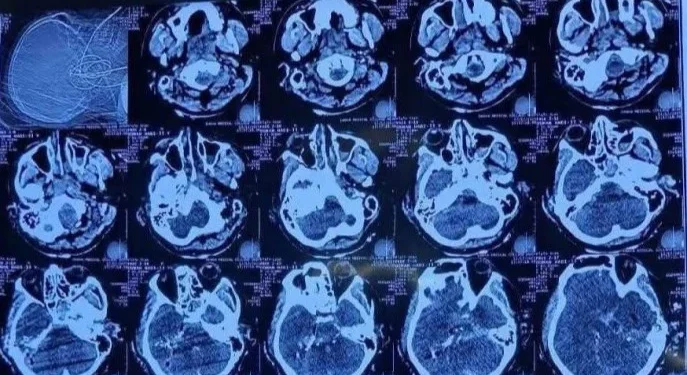

আঘাতের ভয়াবহতা বর্ণনা করতে গিয়ে ডা. সুমন রানা বলেন, ‘ব্রেনের আঘাতটা এমন ছিল যে, গুলি একদিক দিয়ে ঢুকে আরেকদিক দিয়ে বের হয়ে গেছে। যেদিক দিয়ে গুলি ঢুকেছে, অর্থাৎ কানের কাছের হাড়টি খুবই শক্ত। সেটি ভেঙে হাড়ের টুকরাগুলো মস্তিষ্কের ভেতরে ঢুকে আরও আঘাত সৃষ্টি করেছে, যাকে আমরা চিকিৎসার ভাষায় ‘সেকেন্ডারি প্রজেক্টাইল’ বলি। গুলিটি পেছন দিক দিয়ে ঢুকে মাথার অন্য পাশ দিয়ে বের হয়ে গেছে।’